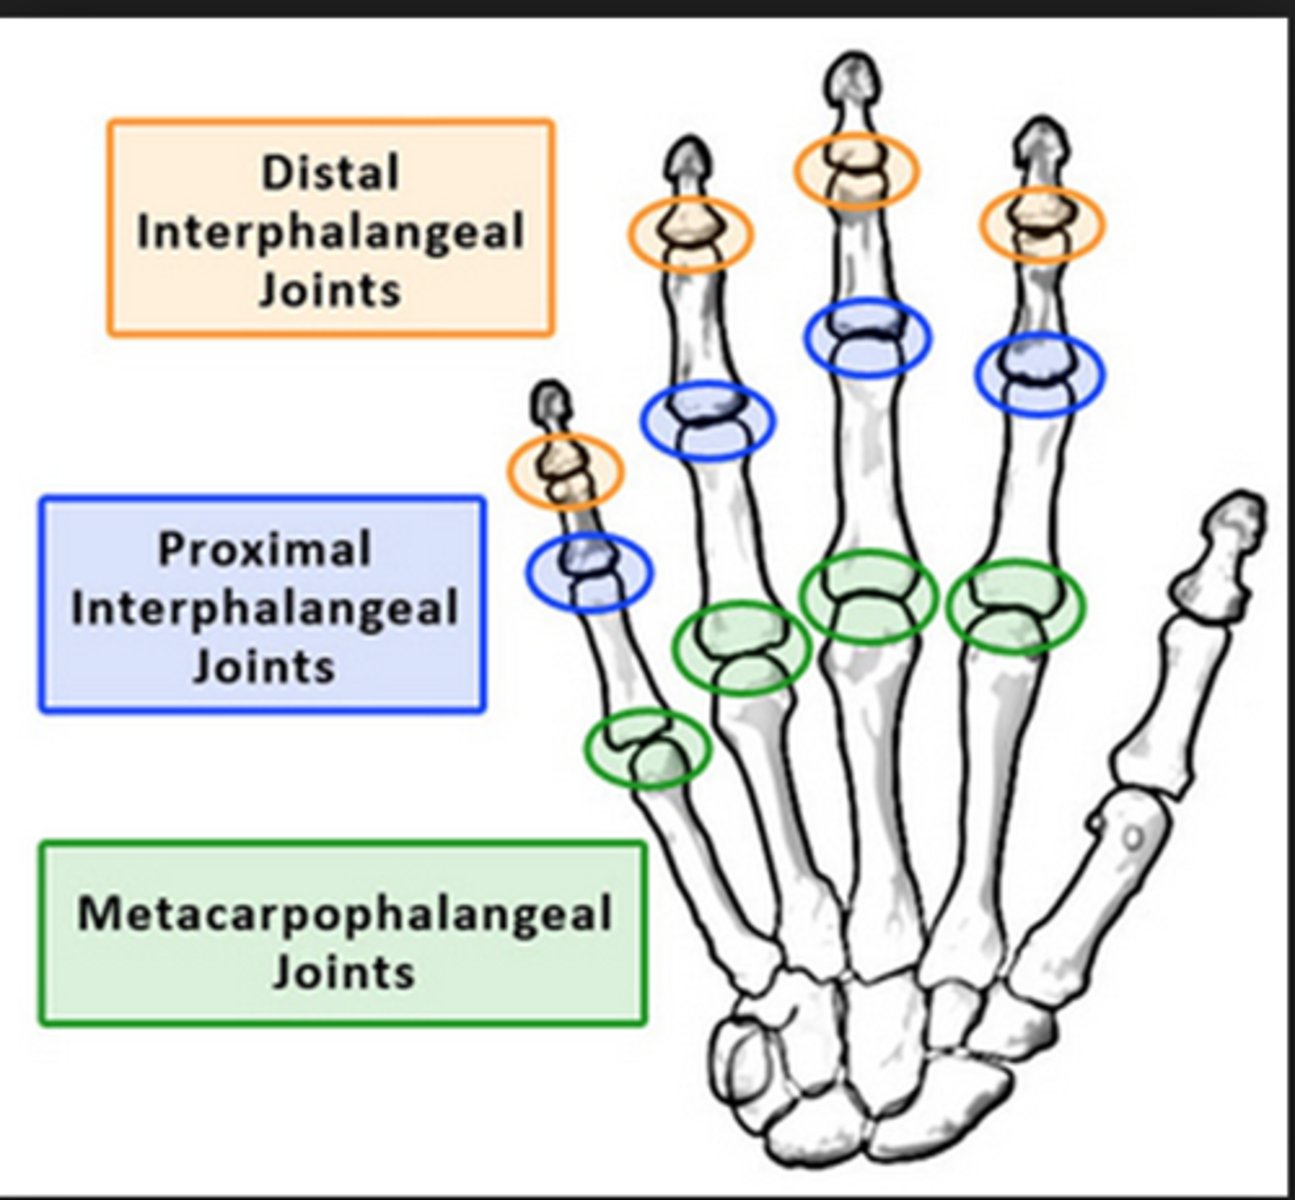

Metacarpophalangeal joints

knuckles; where heads of carpal bones articulate with the proximal phalanges of digits

Proximal interphalangeal joints

between proximal and middle phalanges

Distal interphalangeal joints

Joints between middle and distal phalanges.